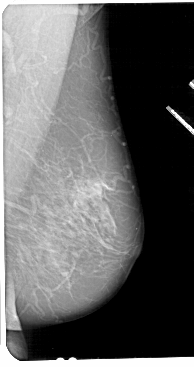

A_1112_1.LEFT_CC

LEFT_CC LINES 5191 PIXELS_PER_LINE 2416 BITS_PER_PIXEL 12 RESOLUTION 43.5 OVERLAY